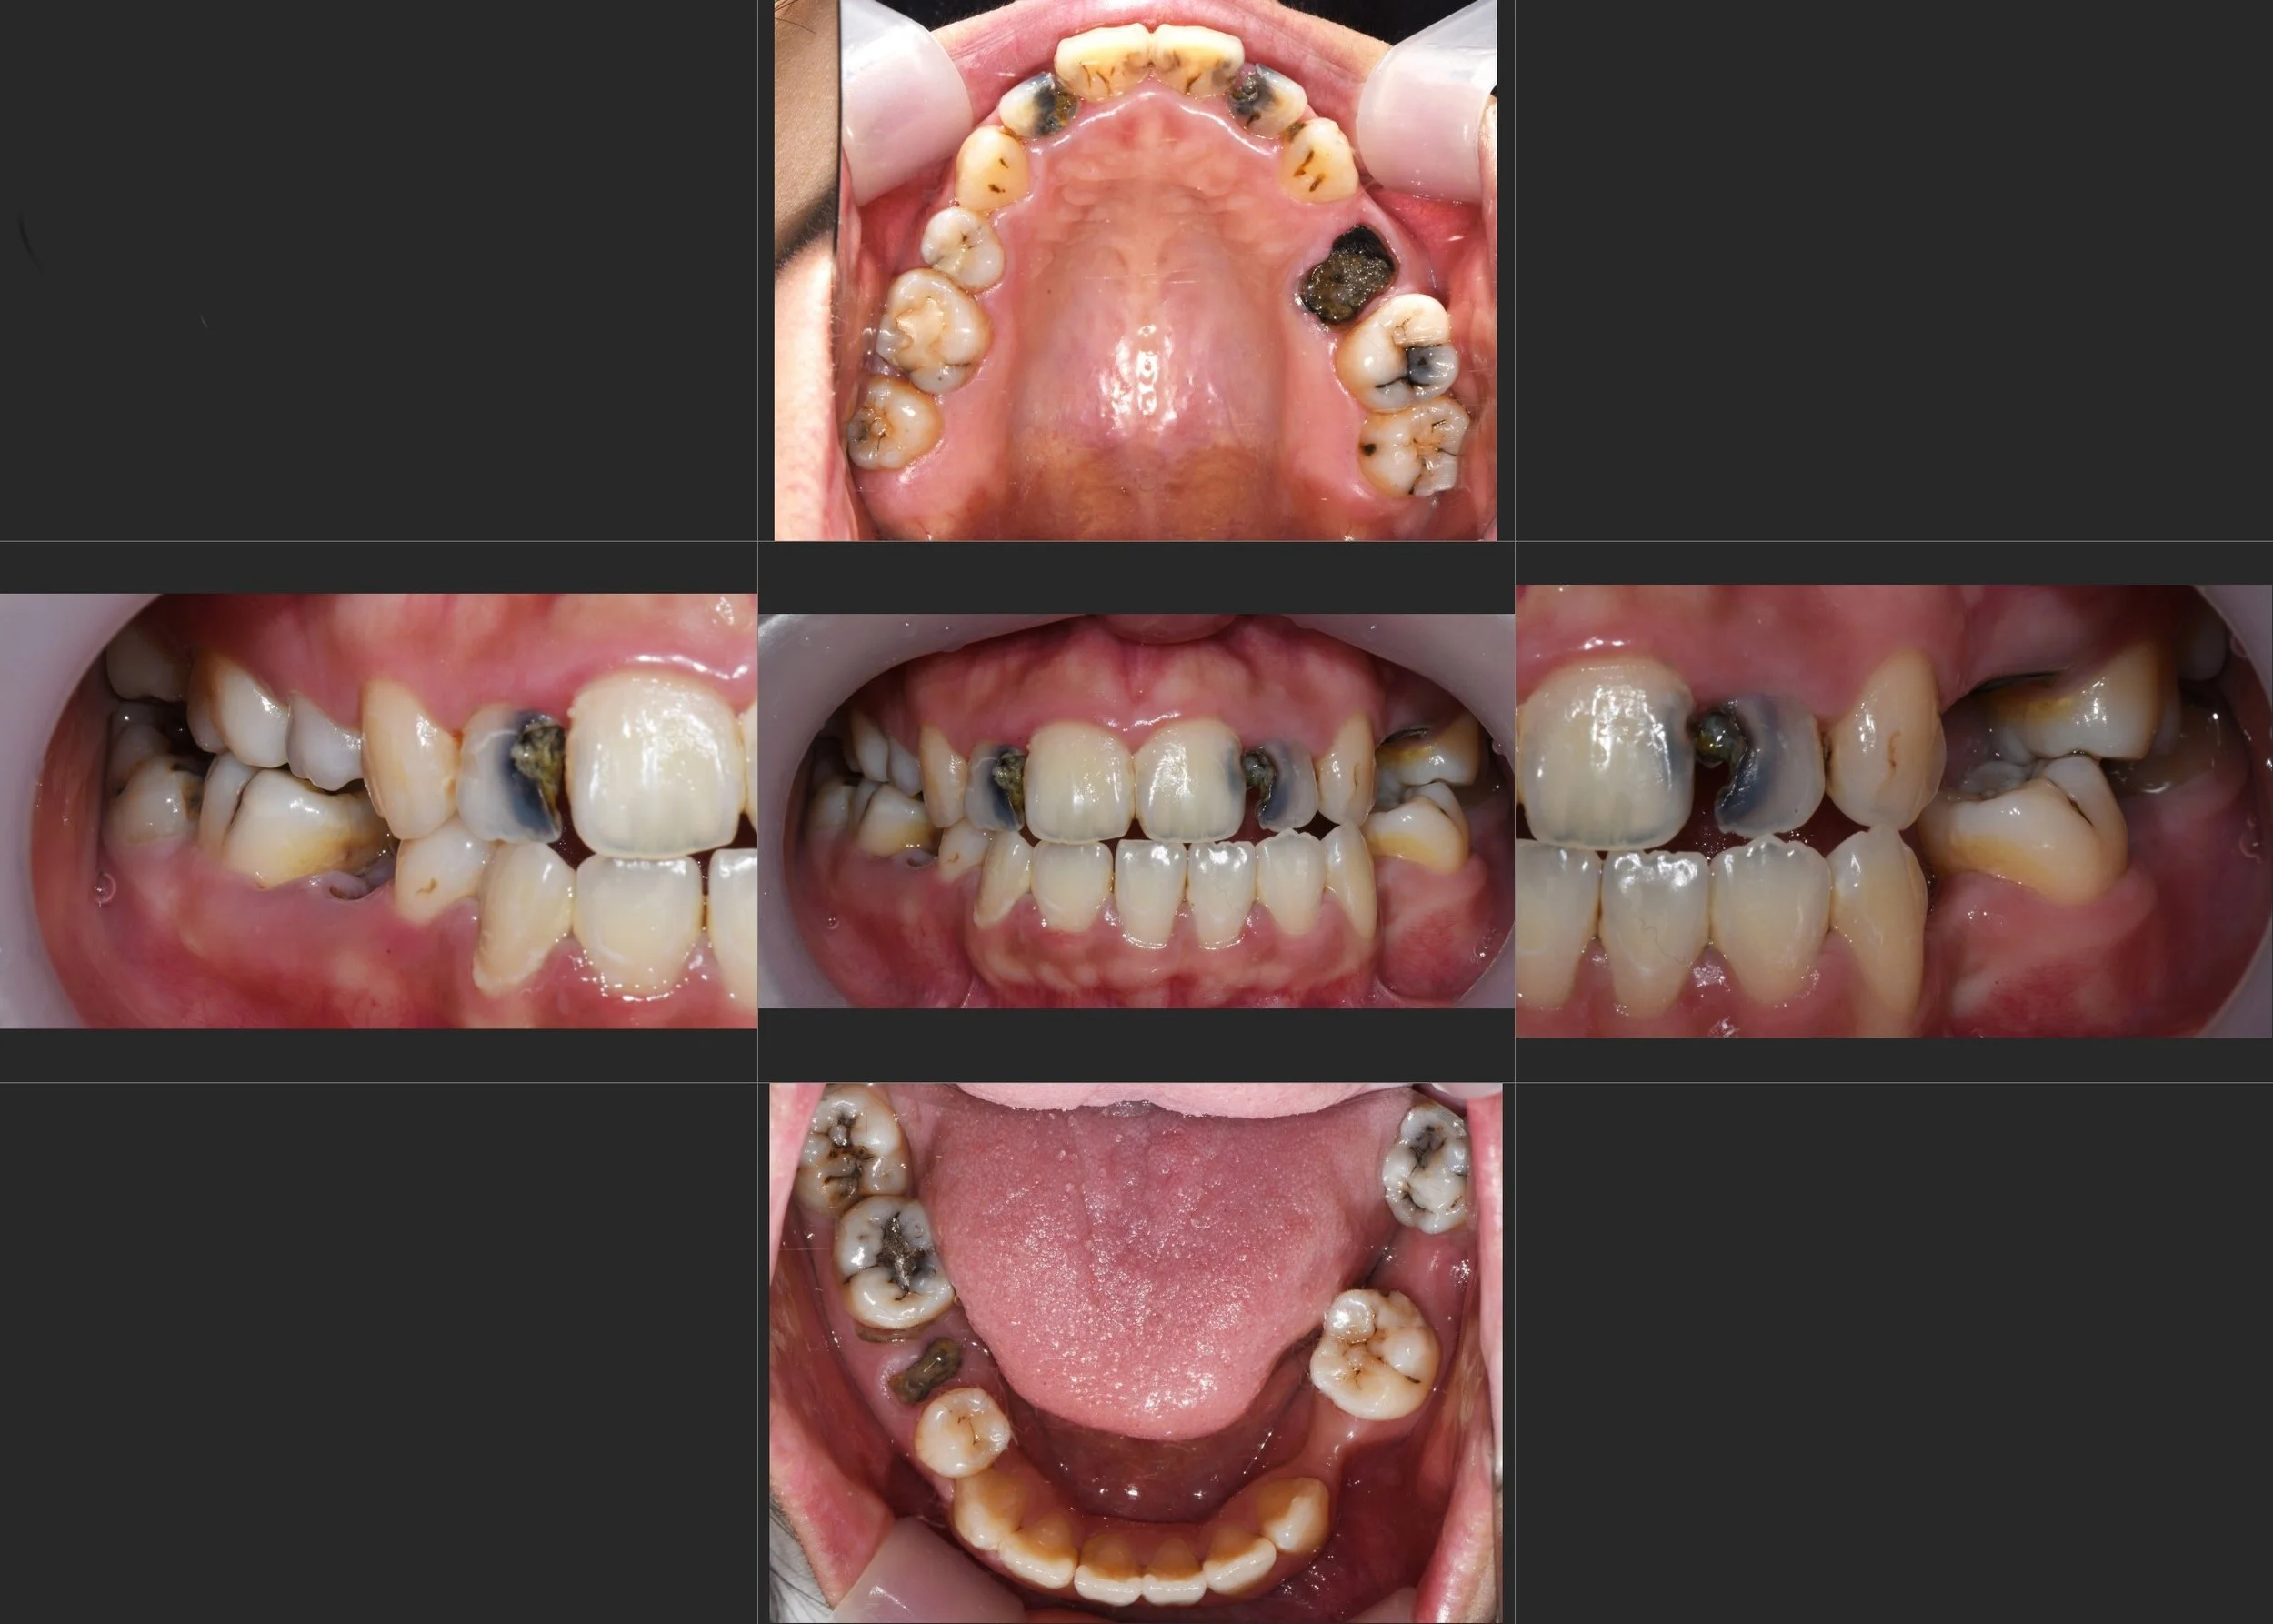

• Pre-operative Intraoral Views Initial intraoral views showing the devastating effects of dental neglect and the urgent need for comprehensive rehabilitation.

INTRA ORAL - BEFORE